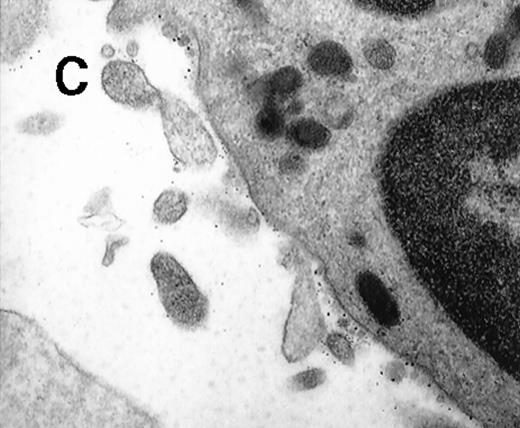

To further visualize the structure of TF on platelets, immunoelectronmicroscopy was performed on thrombi generated ex vivo by perfusing human blood directly from a donor's arm over collagen-coated slides. TF+ pseudopodia extending from PMN leukocytes were found to contact platelets within the thrombus (Figure1). Adhesion molecules present on the leukocyte surface, which may possibly be involved in the adhesion to platelets during thrombus formation, were also identified. A colocalization of CD15 and TF on pseudopodia and small membrane particles was demonstrated by double immunolabeling (Figure 1). To confirm the presence of TF+ particles within thrombi, a human venous thrombus obtained from a patient was examined by immunoelectronmicroscopy. TF+ particles were present within the thrombus and also intermingled with fibrin strands (Figure2).

(A) Electronmicroscopy showing platelets and PMN leukocytes within a thrombus. Note the PMN leukocyte–derived membrane attached to the platelet surface depicted in the boxed field. (B) Closeup examination of the boxed field: the structure double stains for CD15 (10-nm gold grains) and TF (5-nm gold grains). (C) TF on small particle-like structures in proximity to PMN leukocytes.